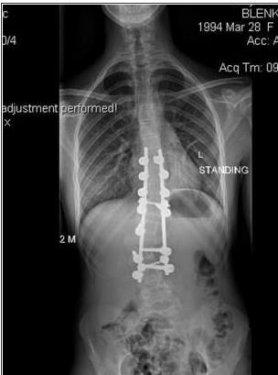

Manken Zoe Blenkinsop dünyaya skolyoz rahatsızlığıyla geldi. Sırtındaki omuru S şeklinde eğri olan genç kız, uzun süre ayağa kalkmakta bile zorlandı.Her seferinde büyük acılar çeken genç kızın sırtında bir yumru oluştu.

11 yaşında teşhis konulan kıza operasyon yapılabilmesi için kemiklerinin yerleşmesi gerektiği söylendi.

Bunun için de 18 yaşına kadar beklemesi gerektiği anlatıldı.

2011 yılında Zoe nihayet ameliyata alındı

Sırtına metal çubuklar yerleştirildikten sonra eğri olan omuru buna bağlandı.

Ameliyat tam 7 saat sürdü.